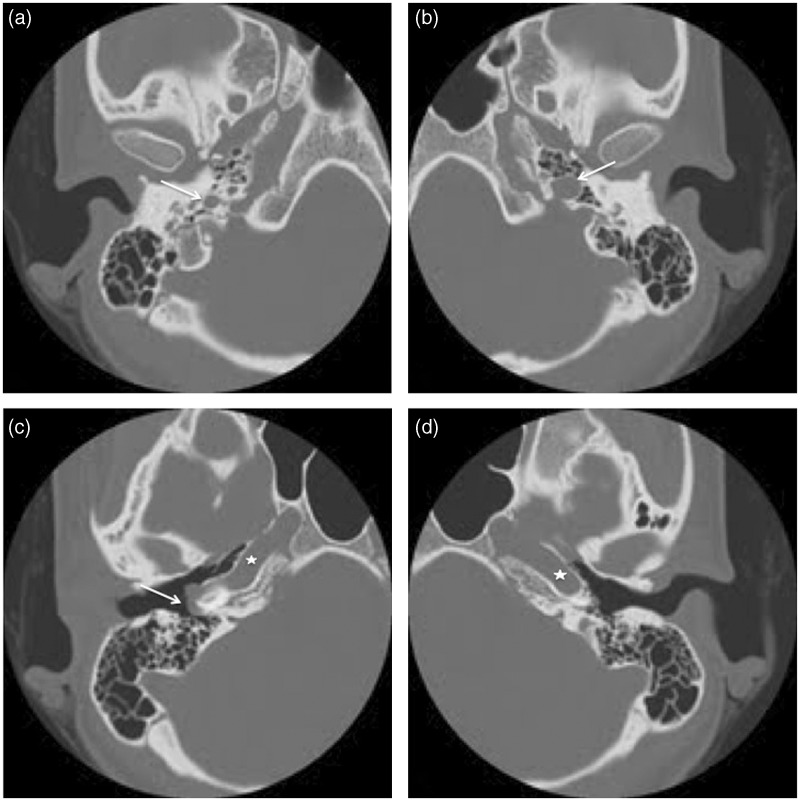

We report a case of a young woman with an aberrant right internal carotid artery (ICA) presenting as a retrotympanic reddish mass. This variant of the ICA represents the collateral pathway that is formed as a result of an embryological agenesis of the cervical segment of the ICA. The embryonic inferior tympanic artery is recruited to bypass the absent carotid segment. This hypertrophied vessel may be seen otoscopically and wrongfully considered to be a vascular middle ear tumor. Informing the otorhinolaryngologist of this important vascular variant not only obviates biopsy but also helps in careful preoperative planning of eventual middle ear procedures.